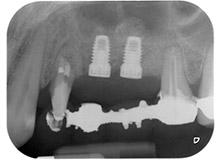

Schließlich wurde die Stelle nach einer Periostschlitzung mit resorbierbarem Nahtmaterial der Stärke 5/0 passiv mit einem koronalen Verschiebelappen vernäht (Abb. 15). Die postoperative Röntgenaufnahme zeigt beide Implantate in korrekter vertikaler Position (Abb. 16).

postoperative Röntgenaufnahme

Abb. 16: Die postoperative Röntgenaufnahme zeigt die eingesetzten Implantate mit apikal erkennbarem Knochenersatzmaterial vom internen Sinuslift. Auch um die Wurzel des Zahns 24 ist Knochenersatzmaterial von der GTR sichtbar.